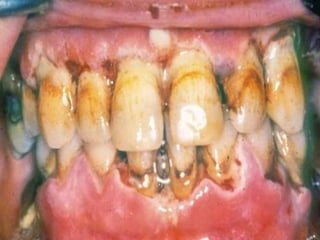

Tooth Decay (Cavities, “Caries”)

• “Processed” carbohydrates, i.e.,

sugars

• Bacterial (Strep. mutans, lactobacilli)

acidic erosion of enamel

• Role of pH, spacing, brushing, Fl

• Tartarplaquecalculus =

bacteria, proteins, cells

Periodontal Disease

• Bacteria

–Actinobacillus

–Porphyromonas

–Prevotella

• Gingiva, periodontal ligaments,

bone, cementum